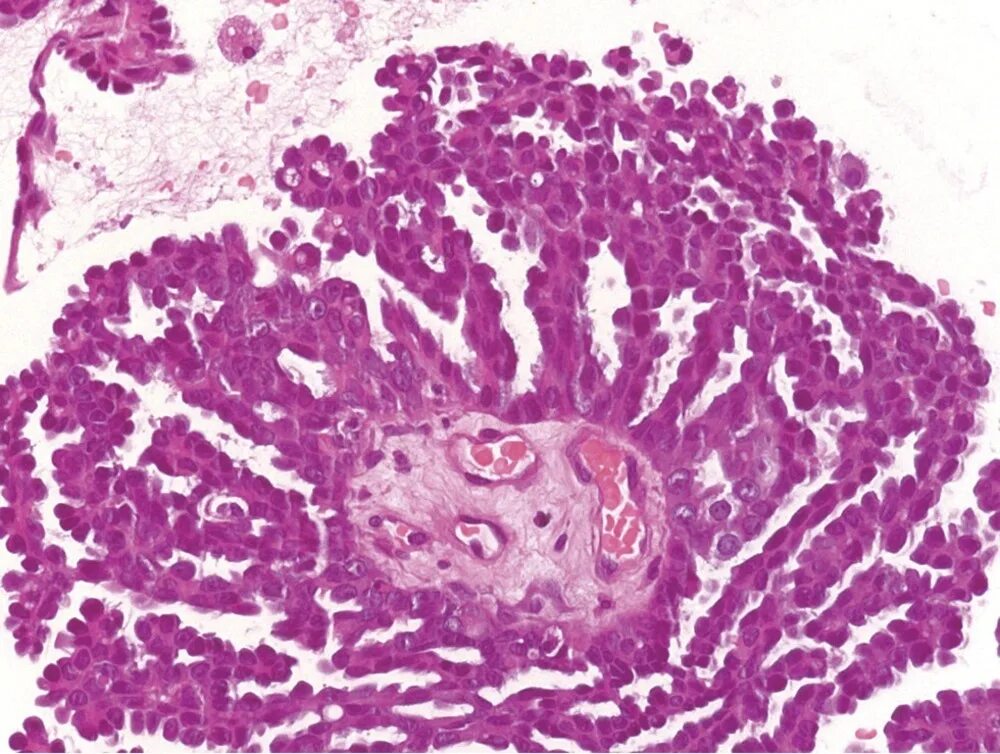

Пограничная гистология